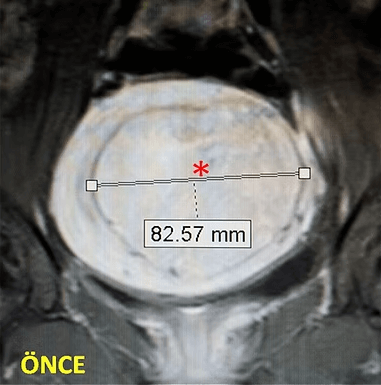

41 yaşında, kabızlık, gaz ve sık idrara çıkma şikayetleri var. Emar’da karını dolduran dev miyom (*) mevcut. Miyomektomi önerilmiş, ancak operasyonda rahimin alınabileceği söylenmiş. Embolizasyondan sonra dev miyomun ve bir başka küçük miyomun öldüğü ve küçüldüğü izleniyor. 7 ay sonra hasta şikayeti kalmamıştır.